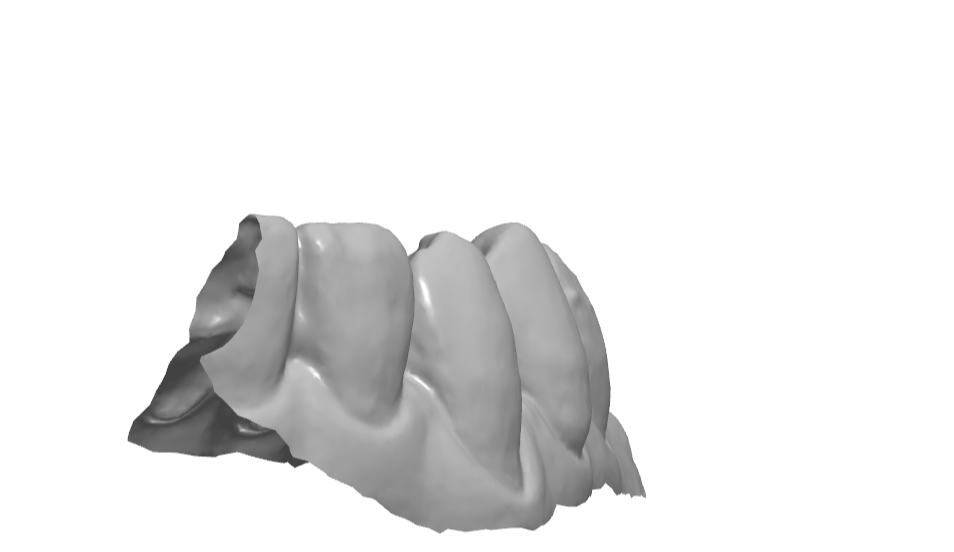

설측 엠브레져 체크.

설측 교두 체크.

설측 교합면쪽 엠브레져 체크.

설면에서의 풍융도 체크.

보이는 방향에 따라 모양이 달라 보인다.